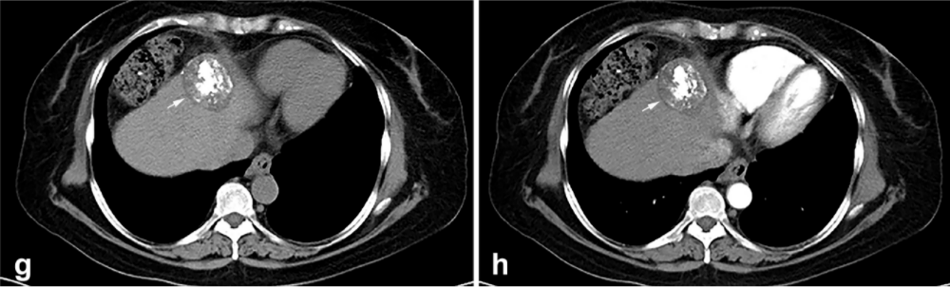

② 冷凍消融后 1 個(gè)月患者的增強(qiáng) CT 顯示HCC獲得緩解。

③ 高危部位術(shù)中消融情況:冠狀面CT圖像經(jīng)多平面重建冷凍消融時(shí),腫瘤完全被冰球(箭頭)覆蓋。